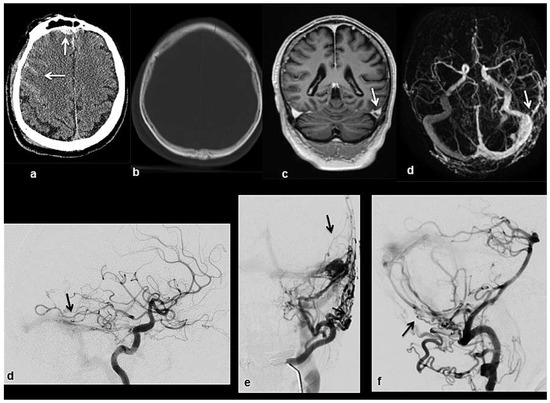

Head and brain trauma: general aspects and neuroimaging

by Johanna Maria Lieb, Christoph Stippich and Meritxell Garcia

In this article the general clinical aspects, imaging indications and different injury mechanisms of traumatic brain injury (TBI) are reviewed. In addition, the different imaging modalities and strategies are presented, including more specific imaging features of the various injuries. Computed tomography (CT) is [...] Read more.

In this article the general clinical aspects, imaging indications and different injury mechanisms of traumatic brain injury (TBI) are reviewed. In addition, the different imaging modalities and strategies are presented, including more specific imaging features of the various injuries. Computed tomography (CT) is the imaging modality of choice in the acute phase owing to its wide availability and short scanning time, as well as to its high sensitivity for the detection of fractures and acute bleeding. Although magnetic resonance imaging (MRI) is superior to CT in many other aspects, it plays no role in the acute phase. MRI, however, has been proven to be useful and complementary to CT in the subacute and chronic stages as well as in the case of inconclusive results on initial CT. Especially the use of standard sequences like fluid attenuated inversion recovery (FLAIR), diffusion and susceptibility weighted imaging (DWI and SWI) have been shown to increase the diagnostic potency in diffuse axonal injury, in mild brain trauma and also in more chronic stages of TBI. The use of more advanced MRI techniques such as diffusion tensor imaging (DTI), magnetic resonance spectroscopy (MRS), functional MRI (fMRI) and magnetic transfer imaging (MTI) can further complete the diagnostic evaluation and give insights into different pathophysiological processes in TBI. Full article